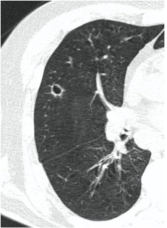

2. Наличие клинических проявлений, указанных в п. 1, в сочетании с характерными изменениями в легких по данным компьютерной томографии (КТ) (см. Приложение 1 настоящих рекомендаций) вне зависимости от результатов однократного лабораторного исследования на наличие РНК SARS-CoV-2 и эпидемиологического анамнеза.

- Изменения при КТ (рентгенографии), типичные для вирусного поражения (объем поражения минимальный или средний; КТ 1 - 2)

- Изменения в легких при КТ (рентгенографии), типичные для вирусного поражения (объем поражения значительный или субтотальный; КТ 3 - 4)

- Изменения в легких при КТ (рентгенографии), типичные для вирусного поражения критической степени (объем поражения значительный или субтотальный; КТ 4) или картина ОРДС.

КТ имеет высокую чувствительность в выявлении изменений в легких, характерных для COVID-19. Применение КТ целесообразно для первичной оценки состояния ОГК у пациентов с тяжелыми прогрессирующими формами заболевания, а также для дифференциальной диагностики выявленных изменений и оценки динамики процесса. КТ позволяет выявить характерные изменения в легких у пациентов с COVID-19 еще до появления положительных лабораторных тестов на инфекцию с помощью МАНК. В то же время, КТ выявляет изменения легких у значительного числа пациентов с бессимптомной и легкой формами заболевания, которым не требуется госпитализация. Результаты КТ в этих случаях не влияют на тактику лечения и прогноз заболевания при наличии лабораторного подтверждения COVID-19. Поэтому массовое применение КТ для скрининга асимптомных и легких форм болезни не рекомендуется.

3. Применение лучевых методов у пациентов с симптомами ОРВИ легкой степени тяжести и стабильном состоянии пациента, возможно только по конкретным клиническим показаниям, в том числе при наличии факторов риска, при условии достаточных технических и организационных возможностей. Методом выбора в этом случае является КТ легких по стандартному протоколу без внутривенного контрастирования или РГ при ограниченной доступности КТ. Использование УЗИ в этих случаях нецелесообразно. Применение КТ исследования в сроки ранее 3 - 5 дней с момента появления симптомов заболевания является нецелесообразным.